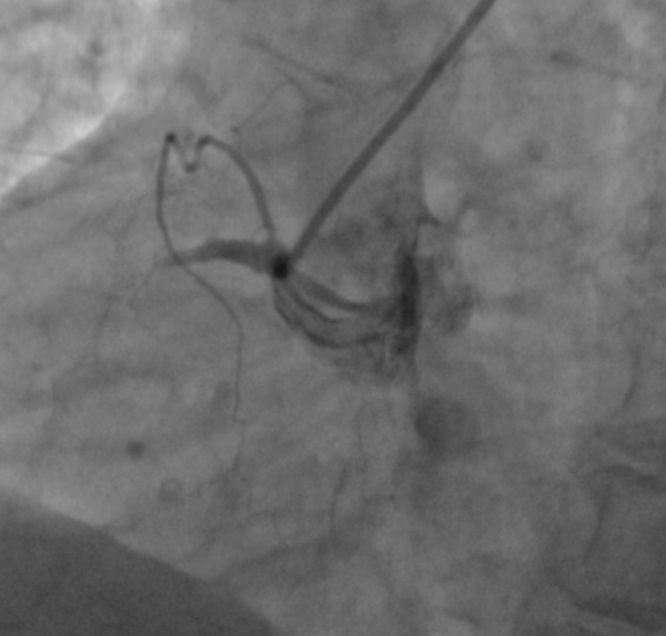

术前造影提示右冠近段闭塞。通讯员供图

随后,经胸痛中心转诊至孝感市第一人民医院进行急诊冠脉造影检查,结果显示熊婆婆的心脏右冠状动脉发生闭塞。